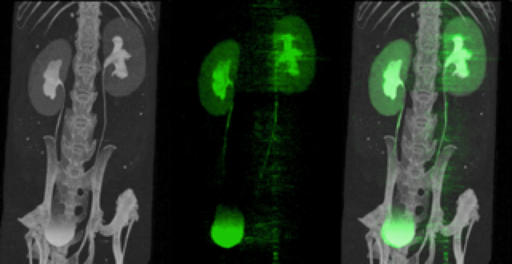

The X and Gamma Imaging team (imXgam) conducts interdisciplinary research activities for ionizing radiation imaging applications in the field of health and energy. These are based on the expertise in electronics and instrumentation of IN2P3, capitalizing its development for large instruments dedicated to high energy physics.

In this context, the imXgam team has built several generations of hybrid pixel cameras for various applications in crystallography and biomedical imaging. We contribute to the development of data acquisition electronics for positron detection by pixelated probes and for rapid gamma imaging in hadrontherapy and we are involved in the development of a Compton camera for nuclear dismantling and hadrontherapy operations.

Development of positron probes for imaging awake, free-moving small animals, in collaboration with IJCLab (Orsay), IPHC (Strasbourg) and CERMEP (Lyon).

- L. Ammour et al. MAPSSIC, a novel CMOS intracerebral positron probe for deep brain imaging in awake and freely-moving rats: a Monte Carlo study. IEEE Trans. Radiat. Plasma Med. Sci. 3 (2019) 302-314

- F. Gensolen et al. MAPSSIC, a communicating MAPS-based intracerebral positrons probe for deep brain imaging in awake and freely-moving rats. EPJ Web of Conferences 225 (2020) 09002

- S. El ketara et al., Characterization of IMIC, an implantable needle-shaped positron sensitive monolithic active pixel sensor for preclinical molecular neuroimaging. Nucl. Instr. Meth. Phys. Res. A 1064 (2024) 169456